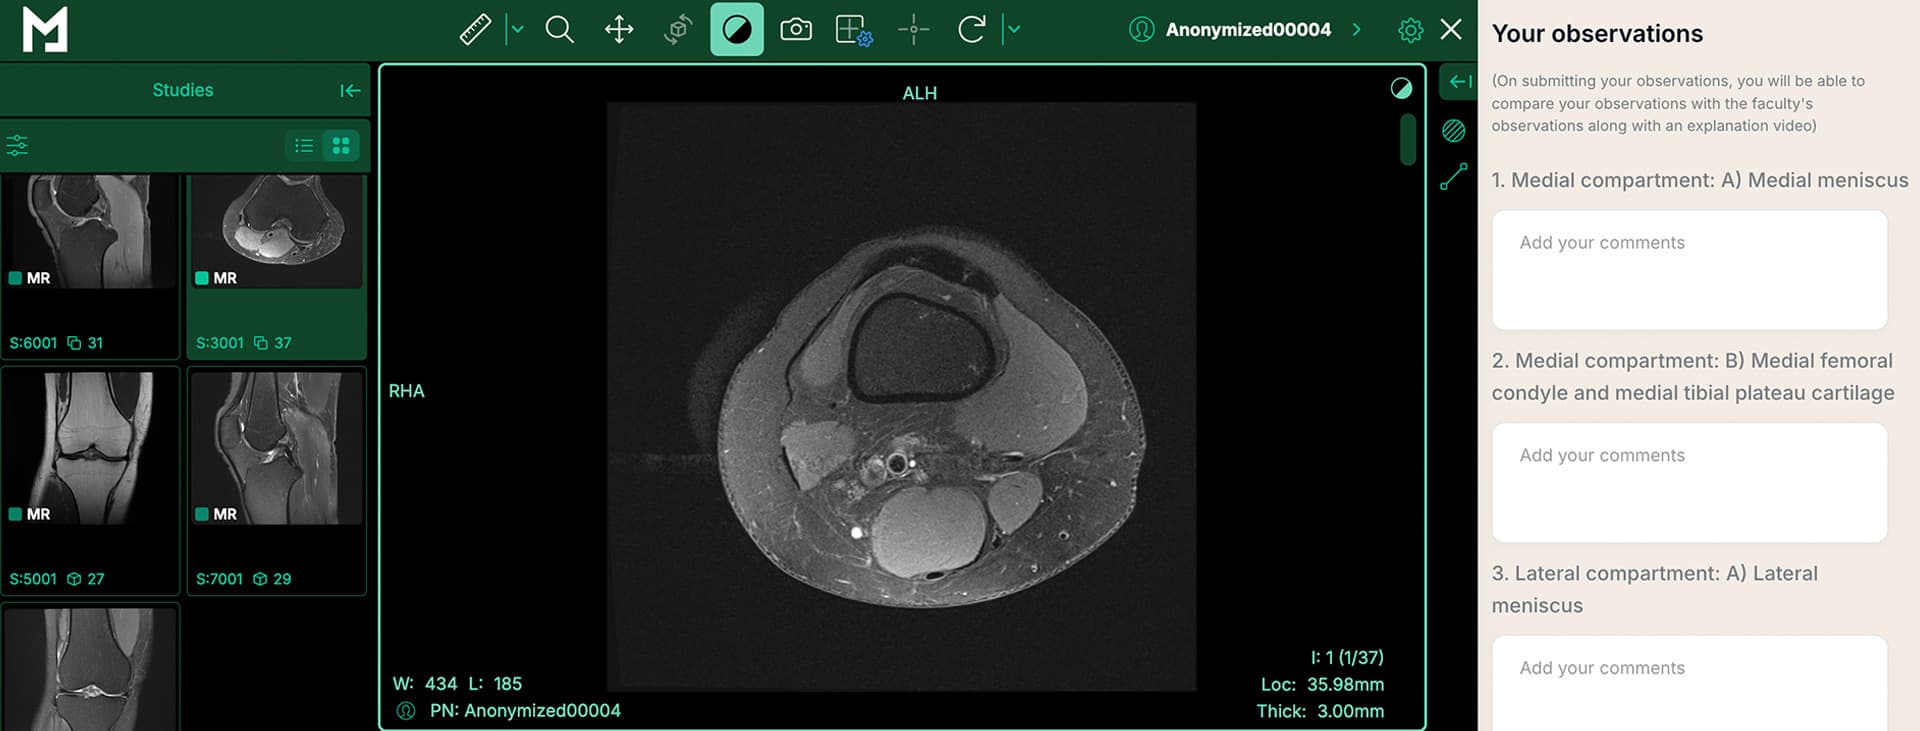

Realistic case simulations to refine diagnostic skills.

Experience realistic case simulations with our advanced DICOM viewer